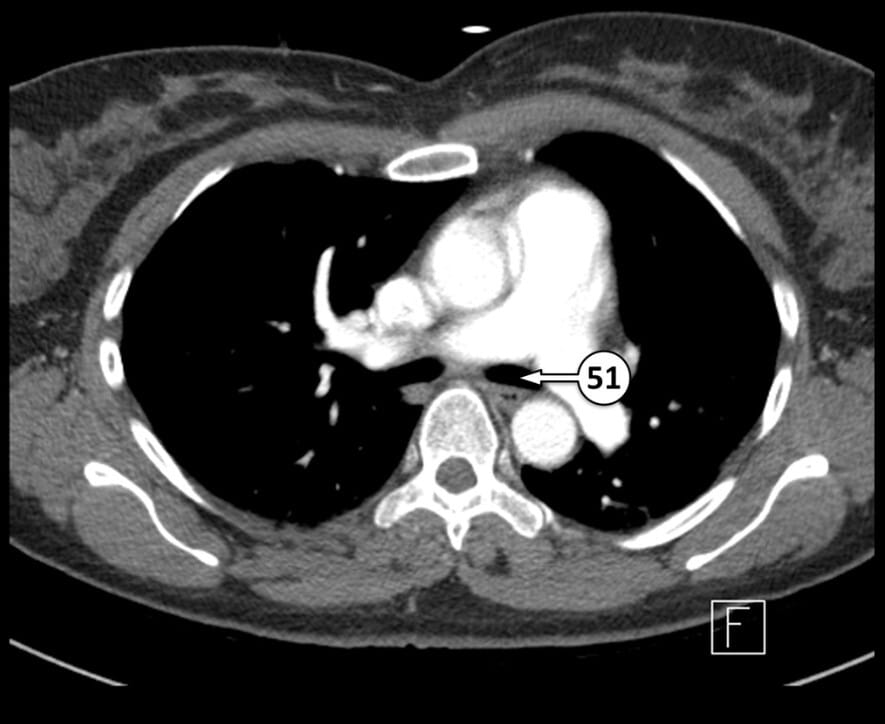

51. left main bronchus